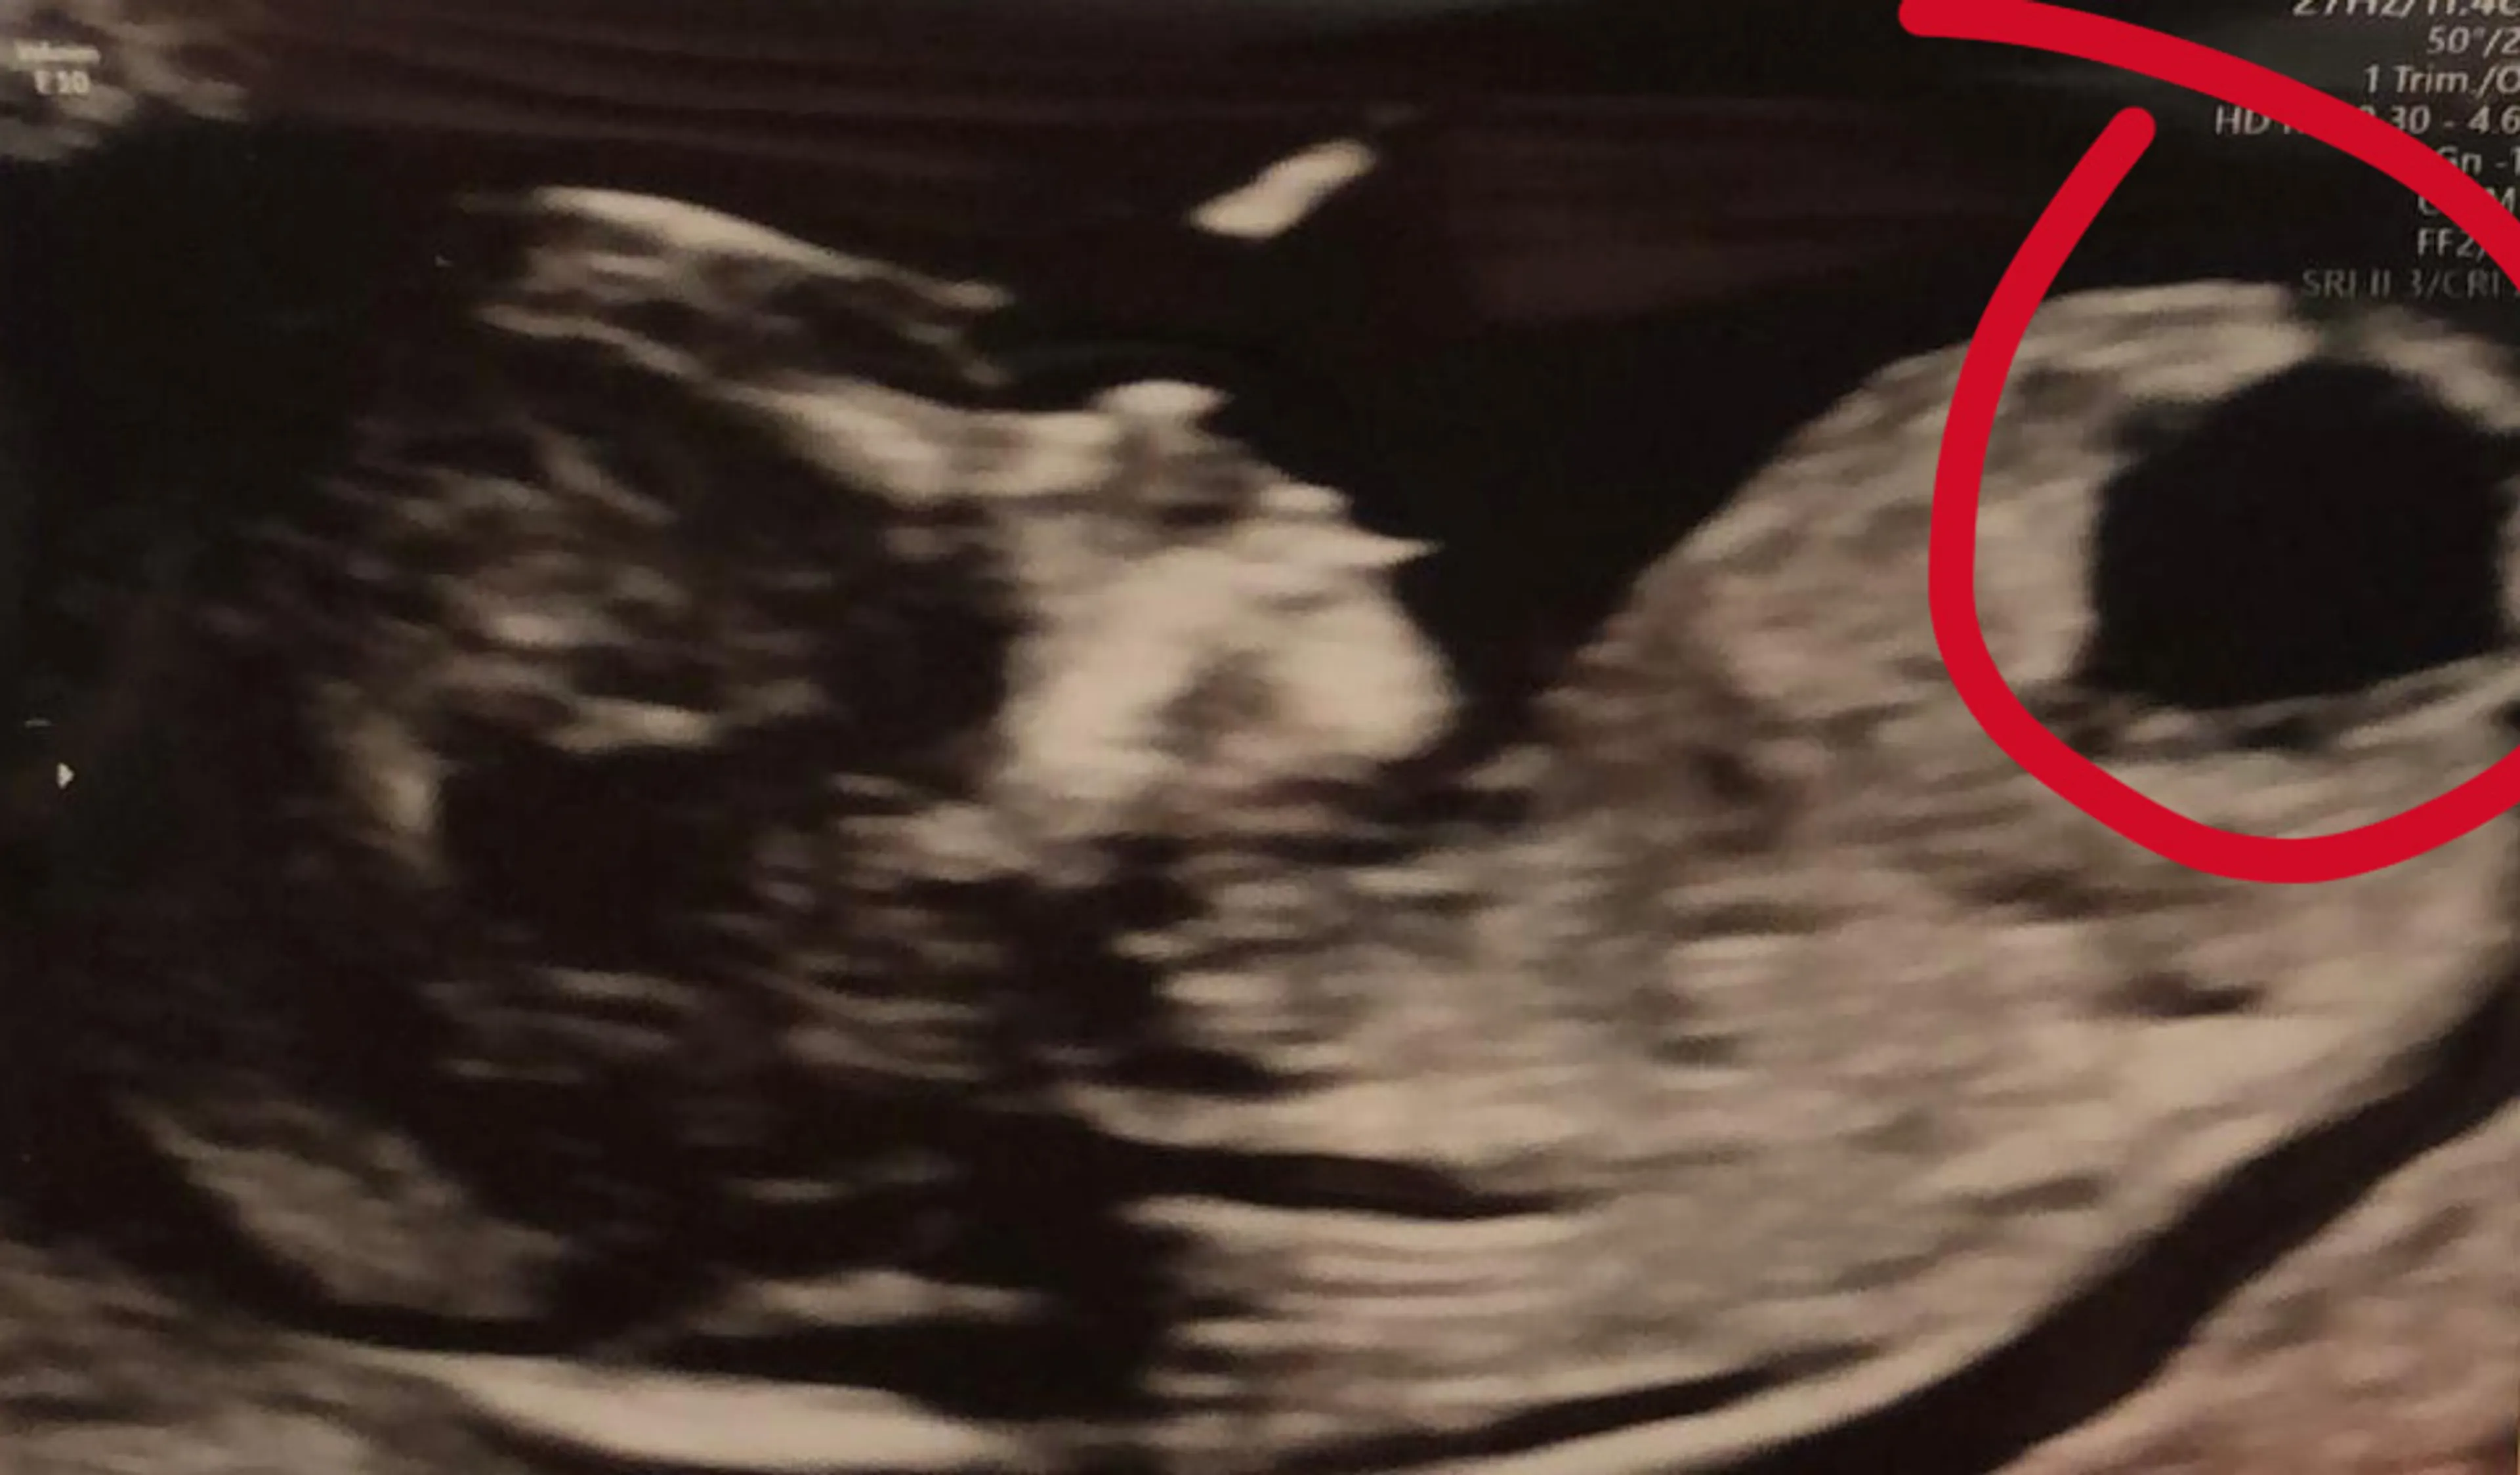

Na de droom voelt Damaris veel rust. Omdat sinds dat moment ook het bloeden was gestopt, belt ze het ziekenhuis voor een nieuwe echo. Die ziet er goed uit. Toch blijkt er al snel weer reden tot zorg. "Toen we een paar weken later bij de verloskundige kwamen, viel het meteen op dat er iets niet goed was. Je hoeft geen medicus te zijn om te zien dat de grote bal die in het lichaampje zat daar niet thuishoorde."

De bal lijkt een vergrote blaas; een teken van een ernstige chromosoomafwijking. "Het was zodanig ernstig, dat het kindje niet levensvatbaar zou zijn. Met zo'n scenario houd je geen rekening… We werden direct doorverwezen naar het ziekenhuis voor uitgebreider onderzoek."

"Naast de bal in het lichaampje (een mogelijke 'megablaas'), had het kindje geen neusbotje en was er iets niet goed met het hoofdje. Allemaal markers voor een ernstige chromosoomafwijking. Ze stelde voor om over een paar weken nog een keer te kijken en raadde ons aan om ook na te denken over het afbreken van de zwangerschap."

De echo geeft al snel meer duidelijkheid. De bal zat er nog steeds, maar er was vooral goed nieuws: het kindje leeft en - in tegenstelling tot de vorige echo - was er nu wél een neusbotje zichtbaar. Ook het hoofdje zag er goed uit. Hoewel er voor de bal verder onderzoek nodig was, kregen ze geweldig nieuws: er was geen sprake van een chromosoomafwijking. "Dat was zo’n bijzonder moment", blikt Damaris terug. "We konden de ergste scenario’s wegstrepen. Dat was het beste nieuws van de dag, van de week, van het jaar!"

Enkele weken later – bij de twintig weken echo – wordt het kindje in Damaris' buik van top tot teen nagekeken. Het onvoorstelbare was gebeurd: "De bal was weg. Er was niks geks meer te zien. Het was helemaal gezond. Alles waar we ons zorgen over maakten, was weg."